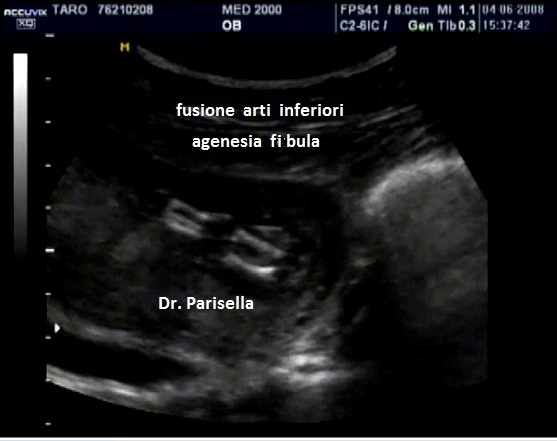

• Displasia scheletrica: ossa lunghe curve, agenesia della fibula, aspetto a ventaglio delle dita dei piedi, polidattilia;